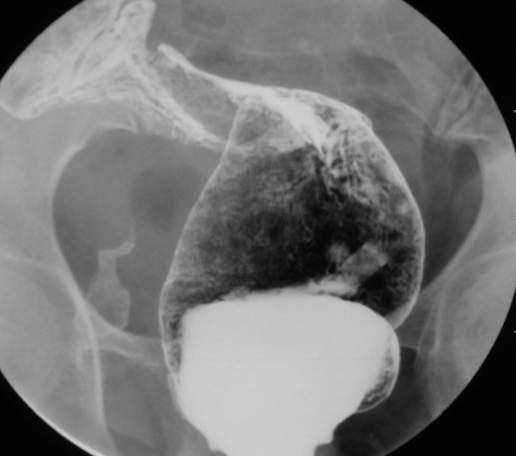

67岁女性,腹痛、腹胀半月余。查:右侧腹部有触痛,可触及肿物。

大家可以和x6045比较一下。x6045病理结果为粘液癌。

常规考虑---结肠癌,不排除诱发肠套叠了。

谢谢大家讨论。与x6045完全不同。本例手术结果为右侧结肠旁沟及盆腔多发脓肿。术后病人恢复良好,现已出院。

感谢楼主反馈结果!造影见果核征,首先考虑肿瘤,即使误诊也应该这样考虑。